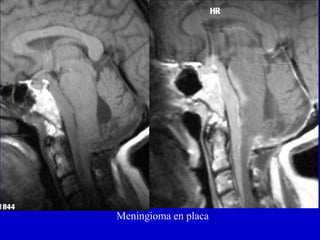

MeningiomaPuede invadir el CAI pero no es habitualmente su epicentroRealce dural

Meningioma en placa